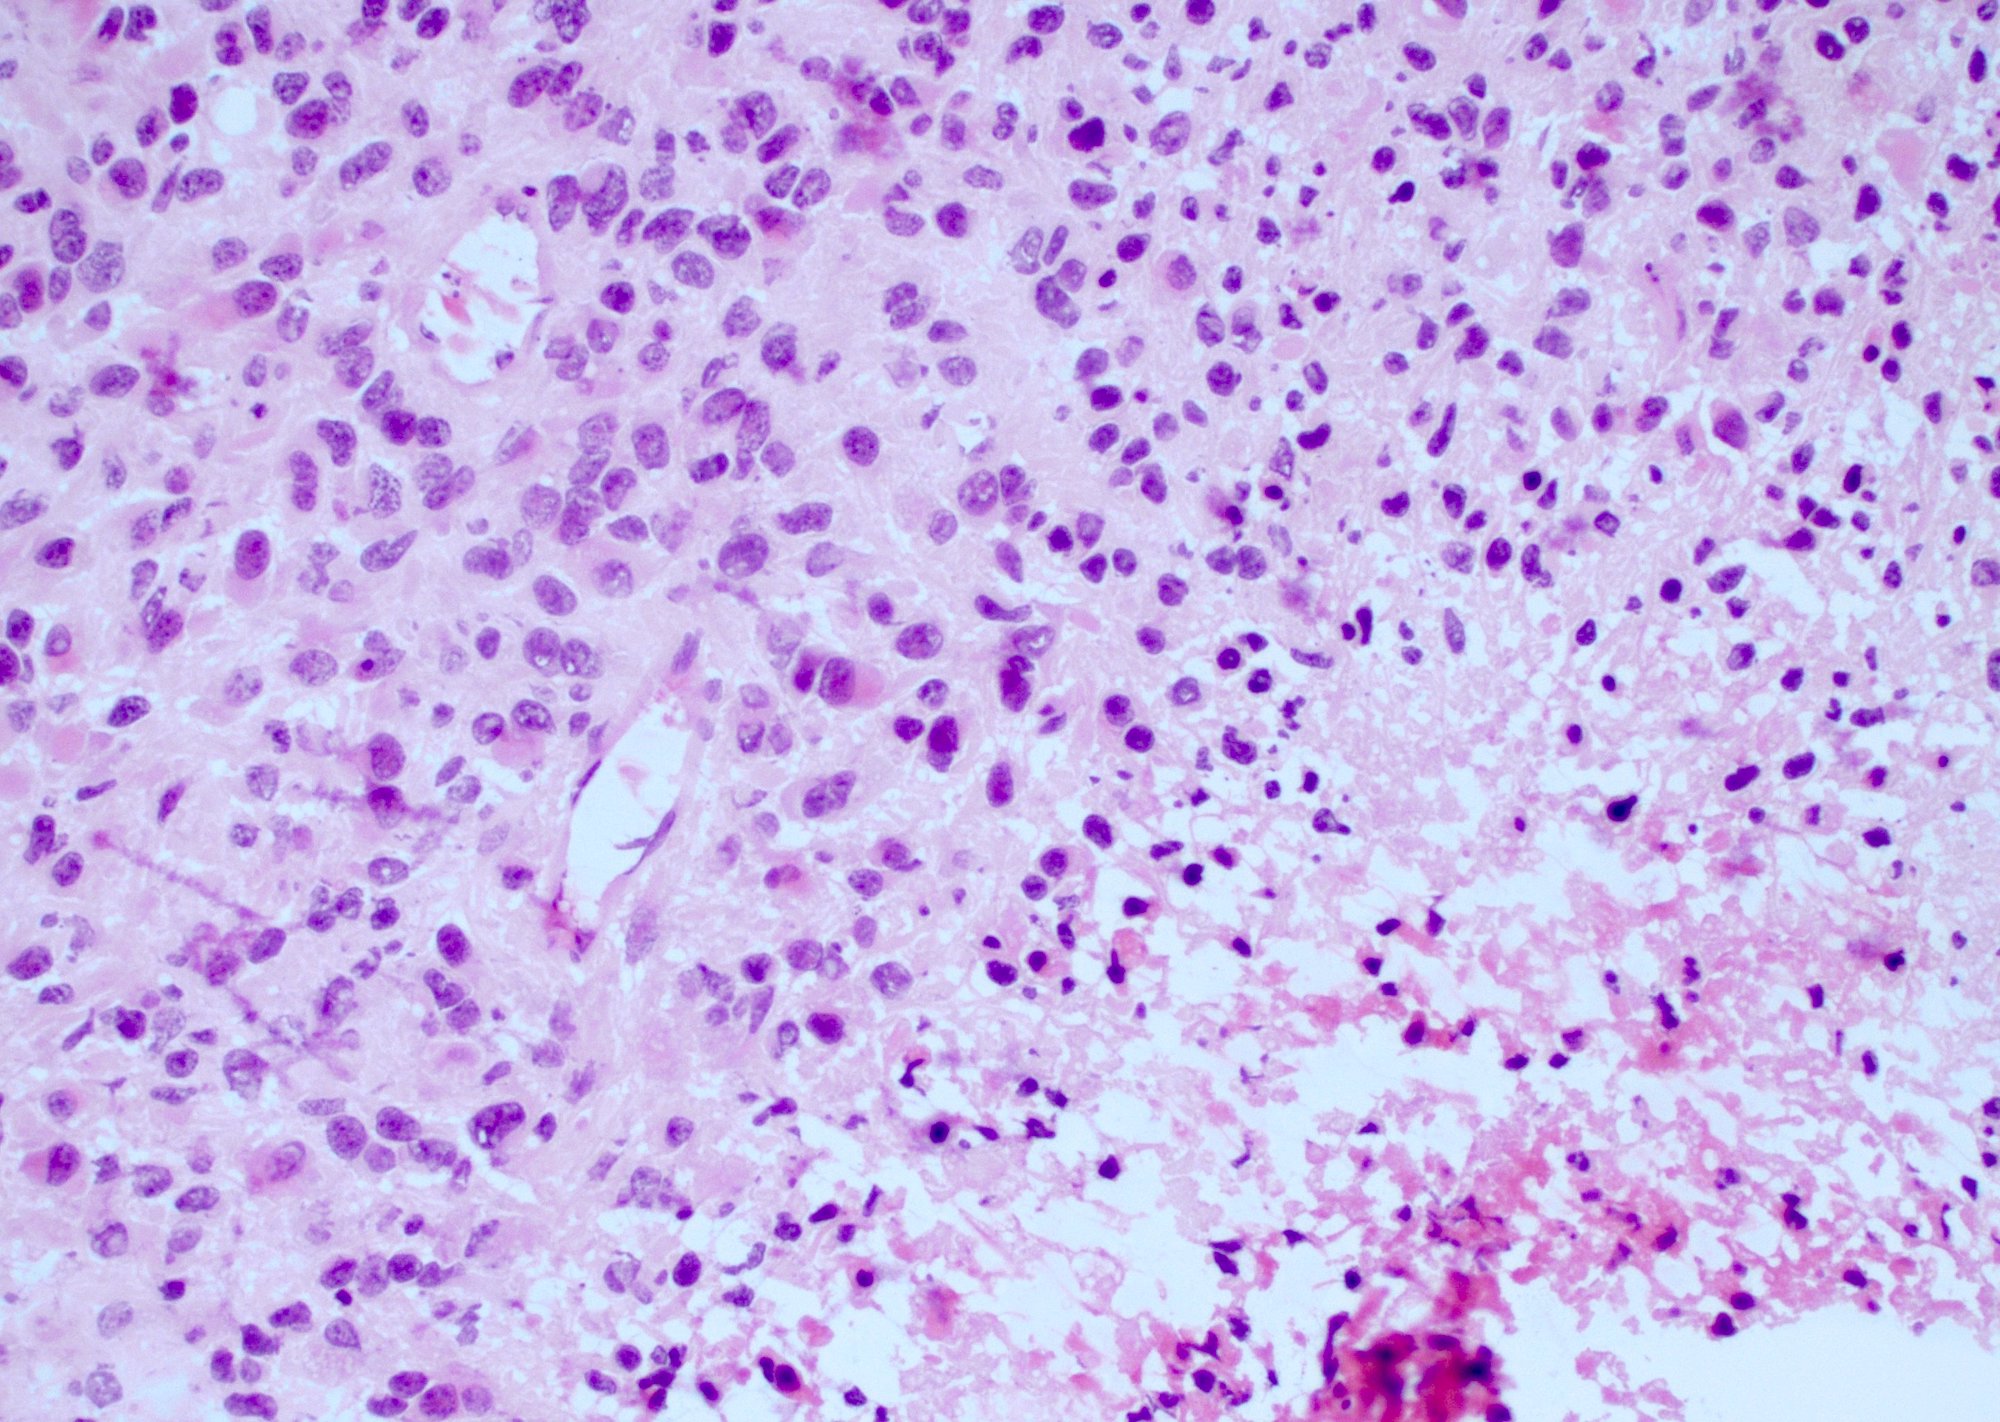

Microscopic (histologic) description

- Infiltrating, hypercellular astrocytic neoplasm often with hyperchromatic, elongated nuclei and irregular nuclear membranes

- Typically mitotically active, though not required if molecular criteria are met

- Microvascular proliferation or necrosis is required for a histologic diagnosis of GBM

- Microvascular proliferation: multilayered, small caliber vessels with glomeruloid appearance (J Neuropathol Exp Neurol 1992;51:488)

- Necrosis: can be geographic or pseudopalisading with neoplastic cells surrounding central necrosis

- Greater association of thrombosis and necrosis in IDH wild type GBM than in IDH mutant grade 4 astrocytomas (Acta Neuropathol 2016;132:917)

- Variable cell morphology: undifferentiated / primitive neuronal cells, astrocytic, gemistocytic, oligodendroglial-like, small cell, lipidized, granular, epithelioid, giant cells, mesenchymal metaplasia and epithelial metaplasia

Microscopic (histologic) images

Contributed by Bharat Ramlal, M.D. and Meaghan Morris, M.D., Ph.D.